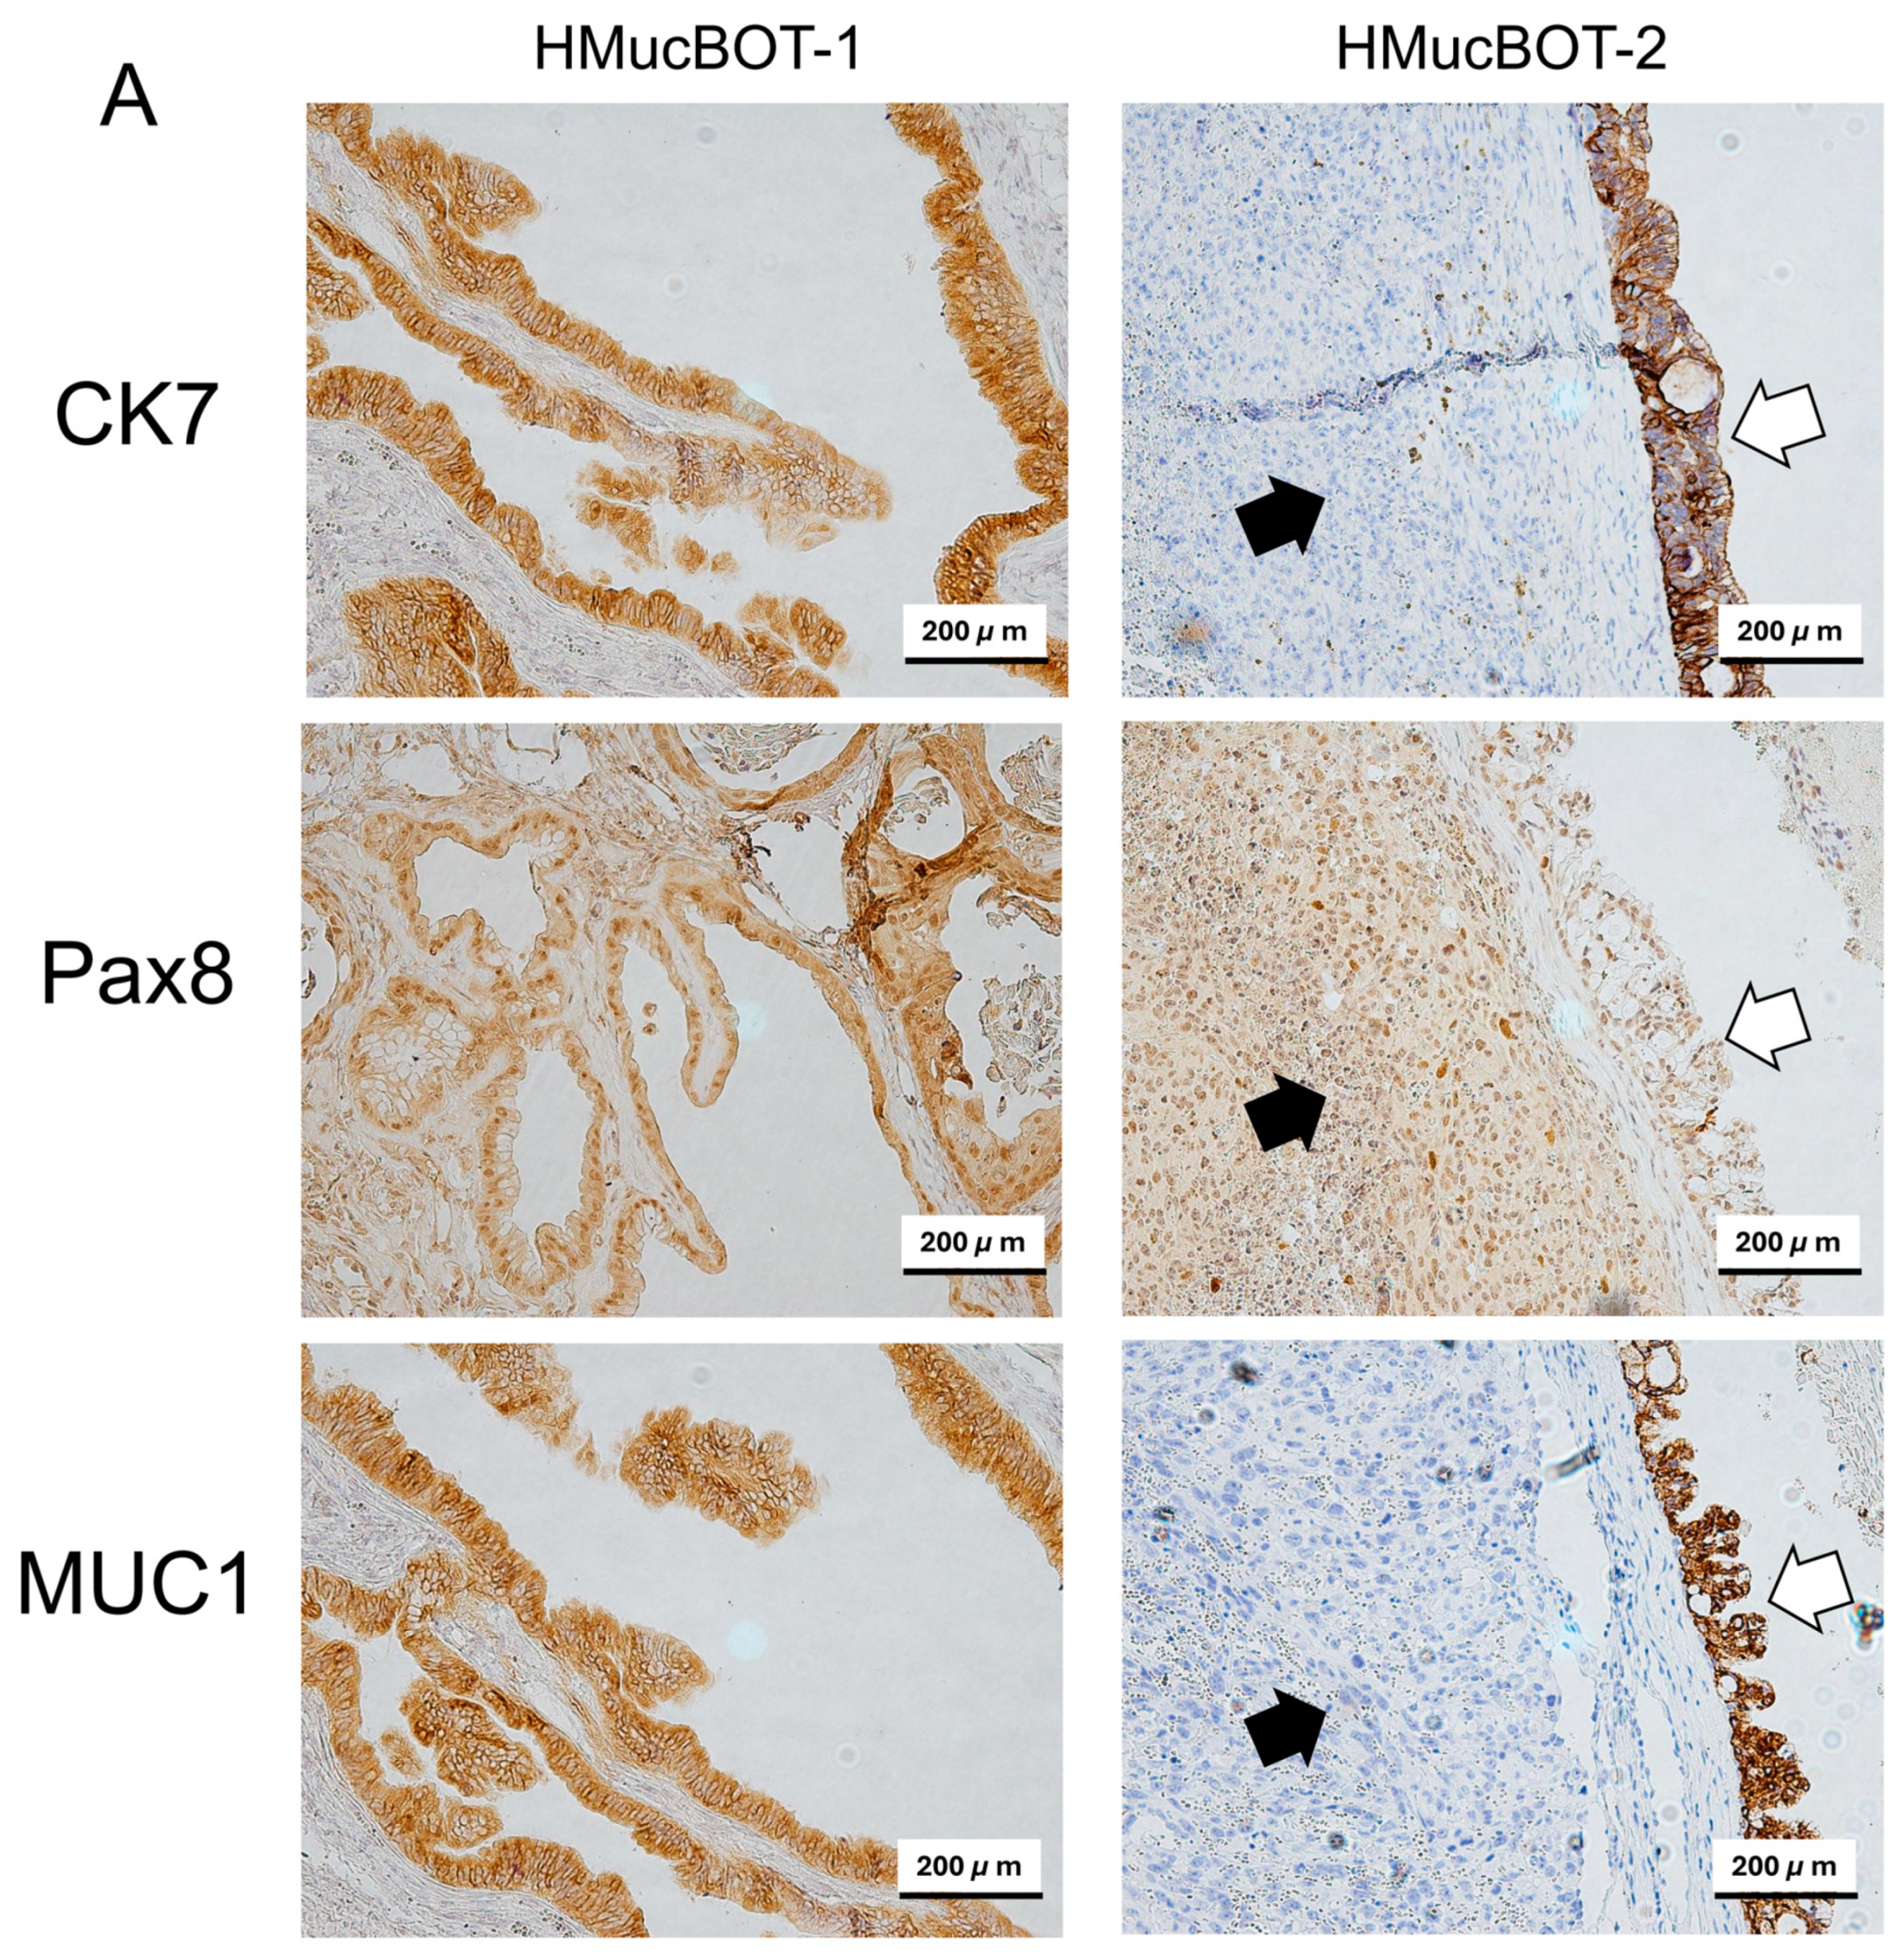

3.6. Characterization of Mouse Xenograft Tumors